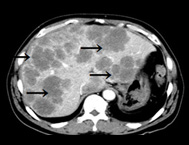

肝臓がんは肝臓にできた悪いできもの(CT画像で黒いぶつぶつ)、紹介したような1~5の肝機能を悪化させたり、ほかの臓器へ転移して命を奪いかねないものです。

肝臓がん

肝臓がんの画像診断

画像を組み合わせることで早期診断が可能